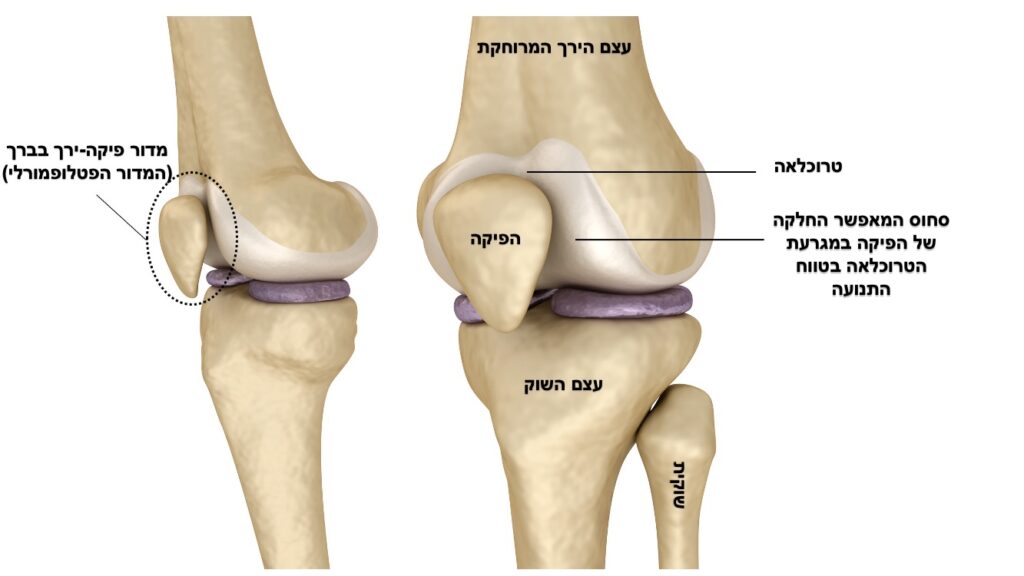

אנטומיה

הפיקה היא עצם השוכנת בתוך הגיד של השריר הארבע ראשי בקדמת הברך. היא מחוברת לרקמות חיבור שונות המייצבות אותה מכיוונים שונים. הפיקה נעה בזמן יישור וכיפוף במגרעת יעודית עבורה בעצם הירך המרוחקת (טרוכלאה). תנועת ההחלקה במגרעת מתאפשרת בזכות רקמת סחוס חלקה אשר עוטפת את הפיקה ואת הטרוכלאה. תפקידה העיקרי של הפיקה הוא תפקיד ביומכני המגדיל את מנוף העבודה של המנגון המיישר של הברך ומעלה את הכח שיכול לייצר השריר הארבע ראשי. תנועה לא תקינה של הפיקה עלולה לגרום לעומסים אבנורמלים באזור זה בברך.